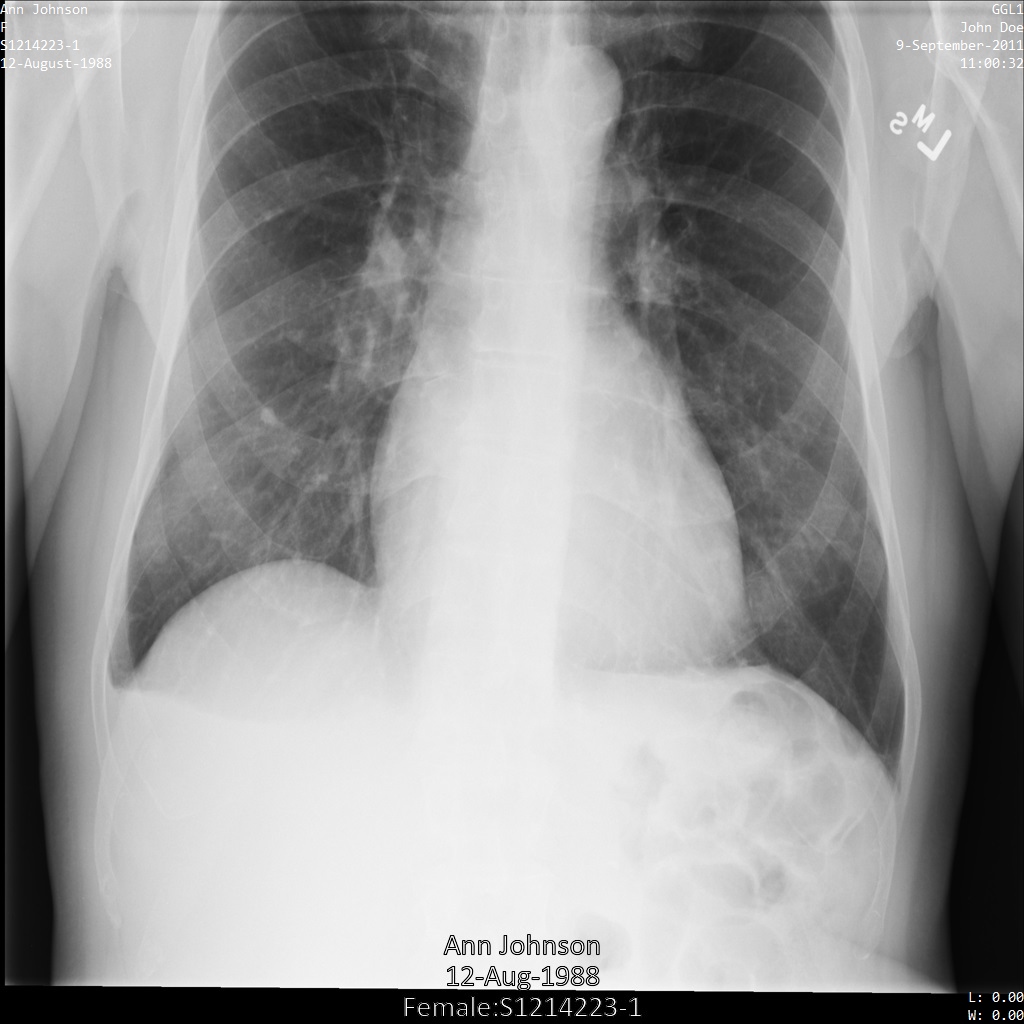

다음 각 섹션에서는 다양한 방법을 사용하여 DICOM 데이터를 익명화하는 방법을 설명합니다. 익명화된 이미지의 출력은 각 샘플에 제공됩니다. 각 샘플은 다음과 같은 원본 이미지를 입력으로 사용합니다.

각 익명화 작업의 출력 이미지를 이 원본 이미지와 비교하여 작업의 효과를 확인할 수 있습니다.

Cloud Healthcare API에 이미지를 제출하면 이미지가 다음과 같이 표시됩니다. 이미지 상단 모서리에 표시되는 메타데이터가 수정되었지만 이미지 하단에 있는 번인 보호 상태 정보(PHI)는 유지됩니다. 번인 텍스트도 삭제하려면 이미지에서 번인 텍스트 수정을 참조하세요.

REST